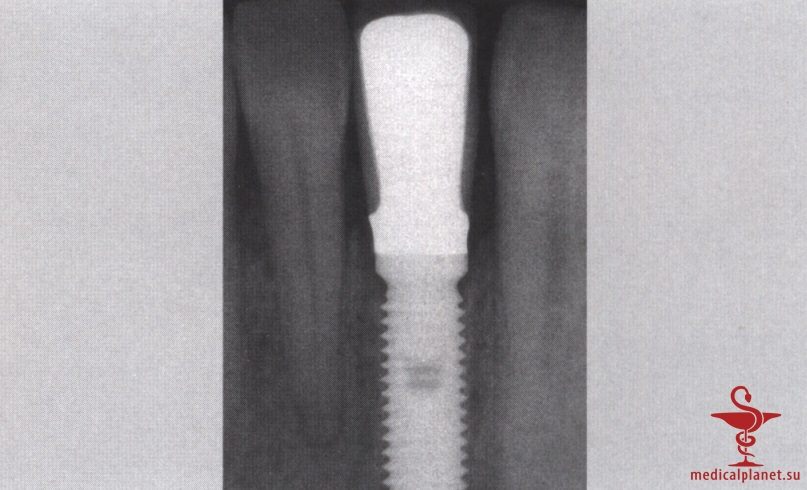

В частности, в эстетически значимой зоне имплантат не следует устанавливать в положении и направлении корня замещаемого зуба, поскольку в большинстве случаев это приведет к слишком вестибулярному положению и избыточному вестибулярному наклону имплантата. Обычно такая ситуация ассоциируется с выраженной рецессией десны, как это описывалось в отдельной статье на сайте (просим Вас пользоваться формой поиска по сайту выше) (рис. 1).

Сначала предполагалось, что уменьшение зазора является предпочтительным, поэтому рекомендовали устанавливать имплантаты максимального диаметра. Данное предположение оказалось ошибочным. В настоящее время доказано, что зазор менее 0,5 мм между костью и имплантатом заполняется новообразованной костной тканью без каких-либо дополнительных манипуляций.4 Более того, следует избегать контакта имплантата с костной стенкой, чтобы не оказывать на нее давление, которое сопровождается резорбцией кости (рис. 4).